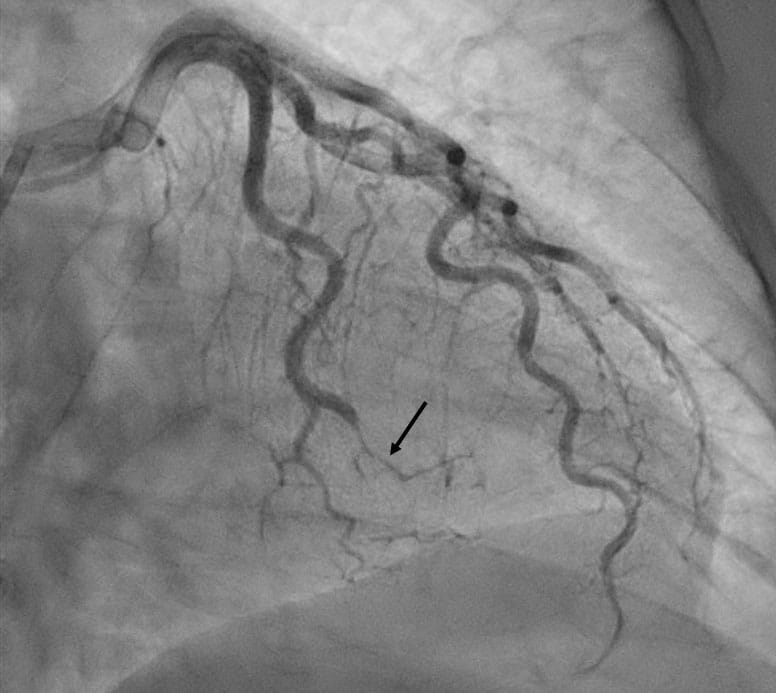

Spontaneous coronary artery dissection (SCAD) is a rare but urgent condition resulting from a sudden tear or bleed within the wall of a coronary artery. SCAD is an underdiagnosed cause of heart attack, acute coronary syndrome and cardiac arrest, and its risk factors and optimal treatment are not yet well-understood. The International SCAD (iSCAD) Registry, funded through the nonprofit SCAD Alliance, is an independent, multicenter data repository aimed at advancing research and improving patient outcomes.

Heart attack blockages resulting from SCAD differ significantly from more common forms of heart attack. “Interventional cardiologists play a crucial role in determining that a coronary dissection is occurring,” says Dr. Gornik. “These patients tend to have a high risk of complication with coronary angioplasty and stenting, and the blockages due to SCAD are often best managed with medications. But the first step is recognizing on the coronary angiogram that the coronary artery narrowing is due to SCAD and not a typical stenosis. I feel fortunate that, at University Hospitals, we have the experts available to recognize SCAD and offer the differentiated care SCAD requires.”